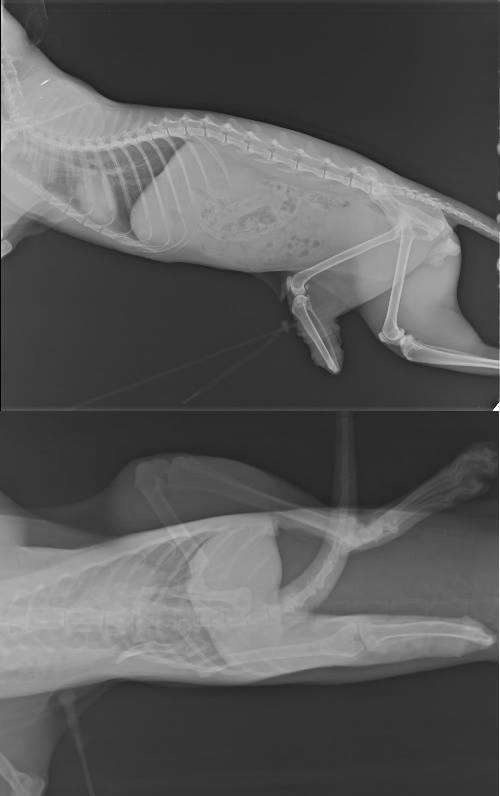

轉而求助於協會配合的醫院,先拍攝X光.血檢..重新做截肢處理

失去一條腿的小錫兵